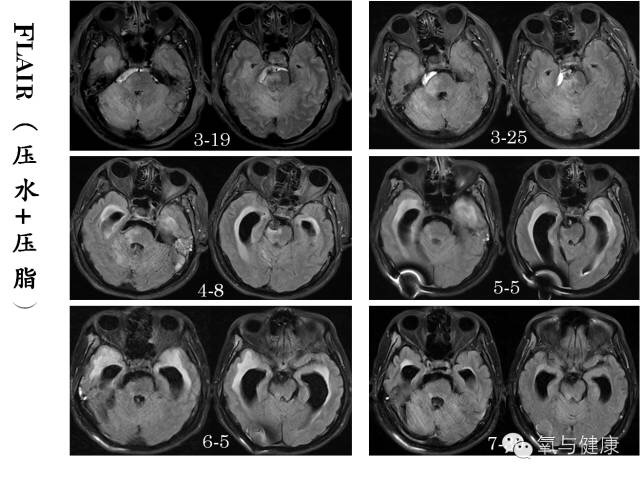

2014年3月12日下午5:20,北京天坛医院,一位男性患者,43岁,因突然出现昏迷,呼吸暂停正在紧急抢救。经紧急气管插管,呼吸机支持等抢救措施,待生命体征平稳后,急诊脑CT检查,确诊为颅内蛛网膜下腔出血,考虑动脉瘤破裂。于19:21分行脑血管介入造影,确诊为基底动脉尖夹层瘤破裂,并行动脉栓塞术。术后自主呼吸恢复,但仍呈浅昏迷状态,随后转入重症监护病房监护治疗,同时进行脑室和腰穿引流,颅内压监测。3月16日(术后第四天)患者昏迷状态加重,医院组织神经外科、神经内科、神经介入科、神经ICU和高压氧科等有关专家紧急会诊。经专家讨论认为再出血可能性很小,除加强监护治疗外,应尽早高压氧治疗。鉴于患者随后两日昏迷进行性加重,3月19日脑核磁影像发现右侧中脑、桥脑和小脑引部和半球广泛急性缺血改变,为挽救患者缺血区脑组织,改善脑干功能,随紧急于当日采用高压氧舱内抢救治疗。高压氧首次治疗后次日患者意识即出现明显好转,随后每次治疗后均有明显改善,后经经高压氧连续治疗6次后神志完全清醒,3月25日、4月8日及5月份脑核磁影像检查原脑缺血范围和程度明显好转(详见核磁影像对比)

3月19日患者意识障碍加重,脑核磁显示:小脑及右侧颞叶可见大片状水肿T2/FLAIR呈稍高信号,DWI呈稍高信号,提示小脑及右侧颞叶大片组织急性缺血性改变,无明显活动性出血;

3月25日和4月8日患者脑核磁复查显示:小脑及右侧颞叶可见大片状水肿T2/FLAIR呈稍高信号,DWI呈稍高信号逐渐减低,范围逐渐缩小,4月8日时DWI信号恢复正常。